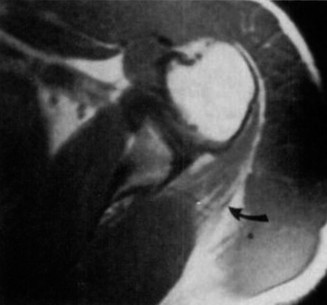

A 24-year-old, male athlete sustains an anterior shoulder dislocation. His MRI is shown in Figure 2–32.

Figure 2–32

Discussion

The correct answer is (A). The MRI demonstrates an HAGL lesion. The MR arthrogram shows fluid extending down the medial humerus and is indicative of an HAGL. Most commonly, with an anterior dislocation, the anterior band of the inferior glenohumeral ligament is torn. With a posterior dislocation, the posterior band is torn creating a reverse HAGL. The ligament tends to tear off the humeral side. These are important injuries to identify as arthroscopic labral repair and capsular shift may be unsuccessful without concomitant repair of the HAGL lesion. Many authors advocate an open approach to repair an HAGL lesion.